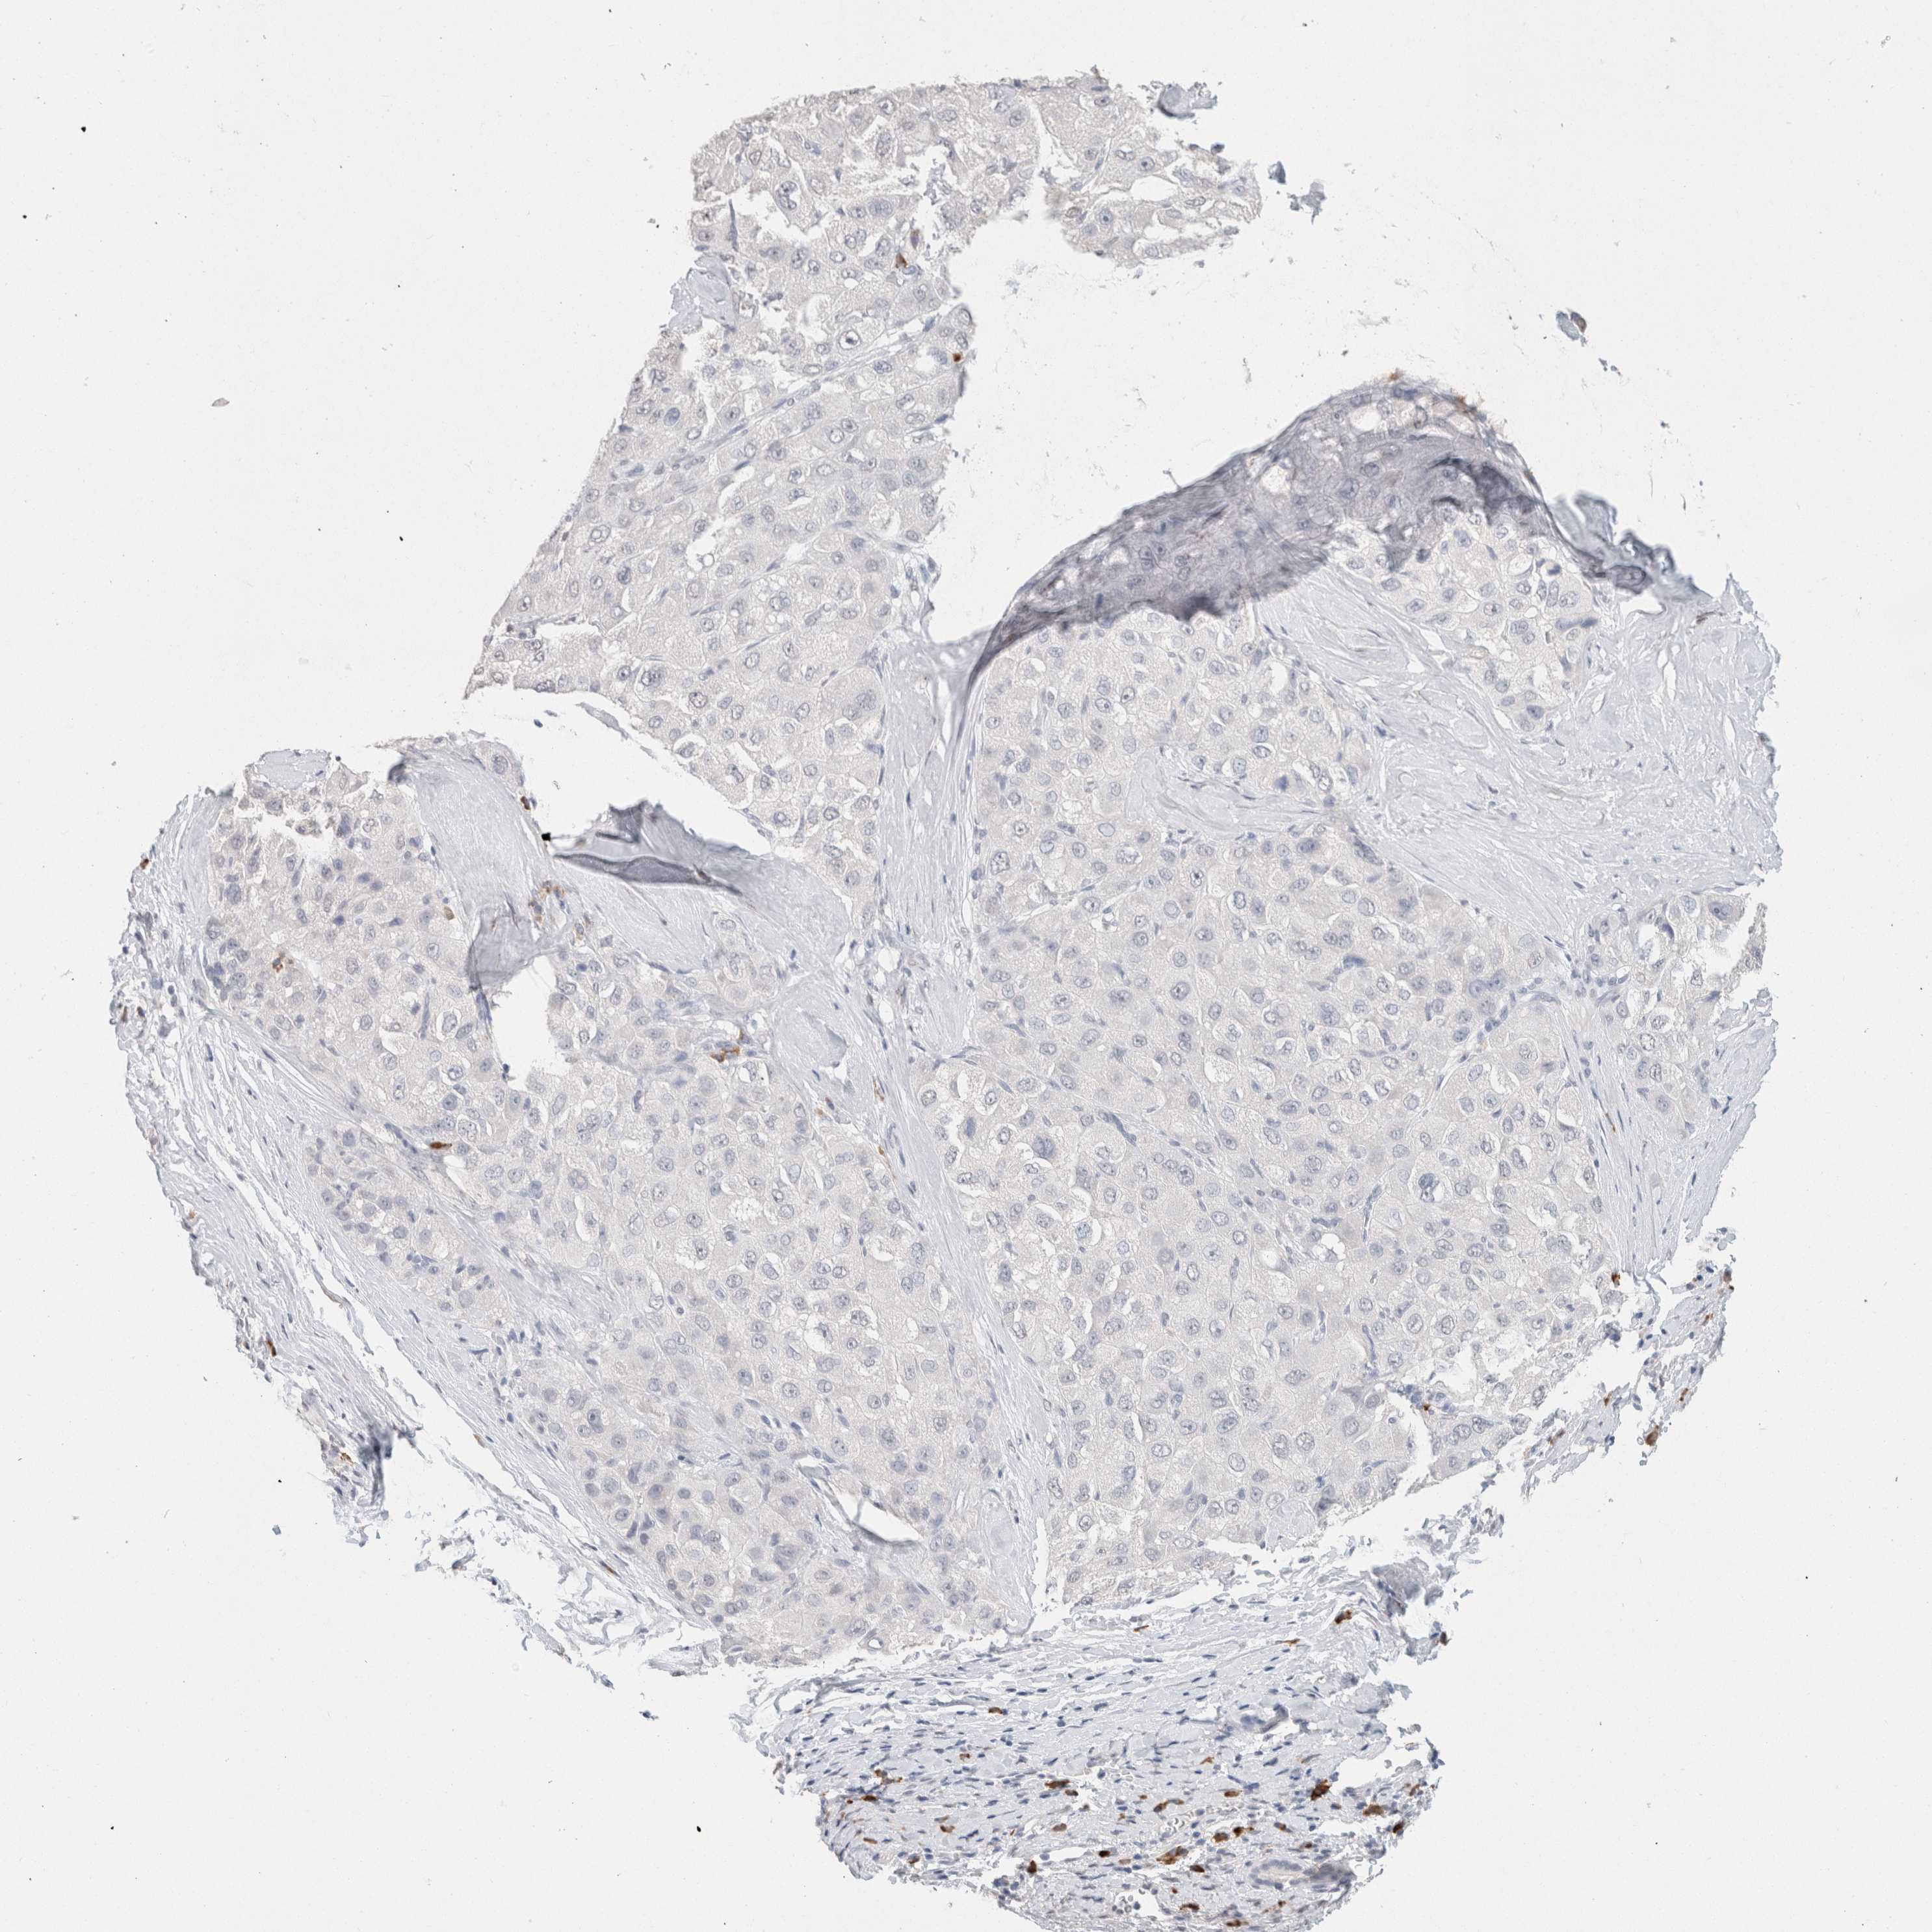

LIVER CANCER - Protein expressioni

A mouse-over function shows sample information and annotation data. Click on an image to view it in a full screen mode. Samples can be filtered based on level of antibody staining by selecting one or several of the following categories: high, medium, low and not detected. The assay and annotation is described here.

Note that samples used for immunohistochemistry by the Human Protein Atlas do not correspond to samples in the TCGA dataset.

Antibody stainingi

Antibody staining in the annotated cell types in the current human tissue is reported as not detected, low, medium, or high, based on conventional immunohistochemistry profiling in selected tissues. This score is based on the combination of the staining intensity and fraction of stained cells.

Each image is clickable and will lead to virtual microscopy that enables deeper exploration of all samples and also displays staining intensity scores, fraction scores and subcellular localization as well as patient and tissue information for each sample.

Antibody HPA050092

Antibody CAB025368

Staining

High

Medium

Low

Not detected

Intensity

Strong

Moderate

Weak

Negative

Quantity

>75%

75%-25%

<25%

None

Location

Nuclear

Cytoplasmic/membranous

Cytoplasmic/membranous,nuclear

Carcinoma, Hepatocellular, NOS

Cholangiocarcinoma